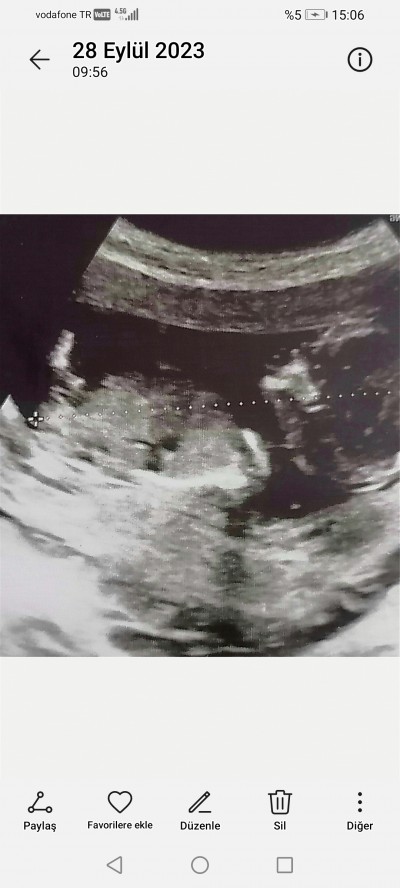

13 haftalık 3 gunluk doktora cinsiyet hakkında hiçbirsey söylemedi merak ediyorum nub teorisi dogruluk payı cok oldugunu duydum sizce ne olabilir cinsiyeti

image